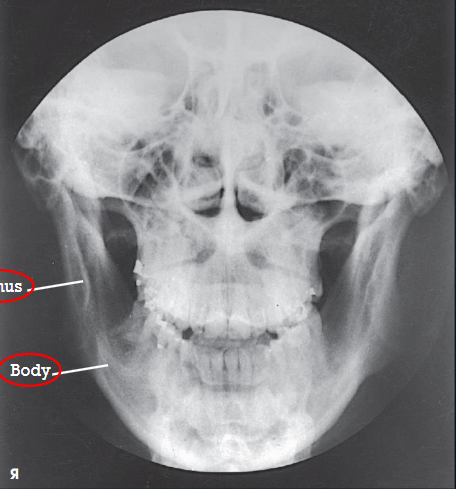

AP axial (modified Towne) zygomatic arches

patient position:

upright or supine

part position:

MSP perpendicular to midline

OML perpendicular to IR

may use IOML if patient can’t flex neck enough

increase in CR angle

respiration suspended

CR:

OML: 30 degrees caudad, enters glabella 1 inch above the nasion

IOML: 37 degrees caudad

collimation:

1 inch beyond the lateral sides of the face, superiorly to the top of the forehead, and inferiorly to the chin

AP axial (modified Towne) zygomatic arches image criteria

both zygomatic arches, free of superimposition

no overlap of arches by mandible

no rotation

symmetric arches

arches projected lateral to mandibular rami